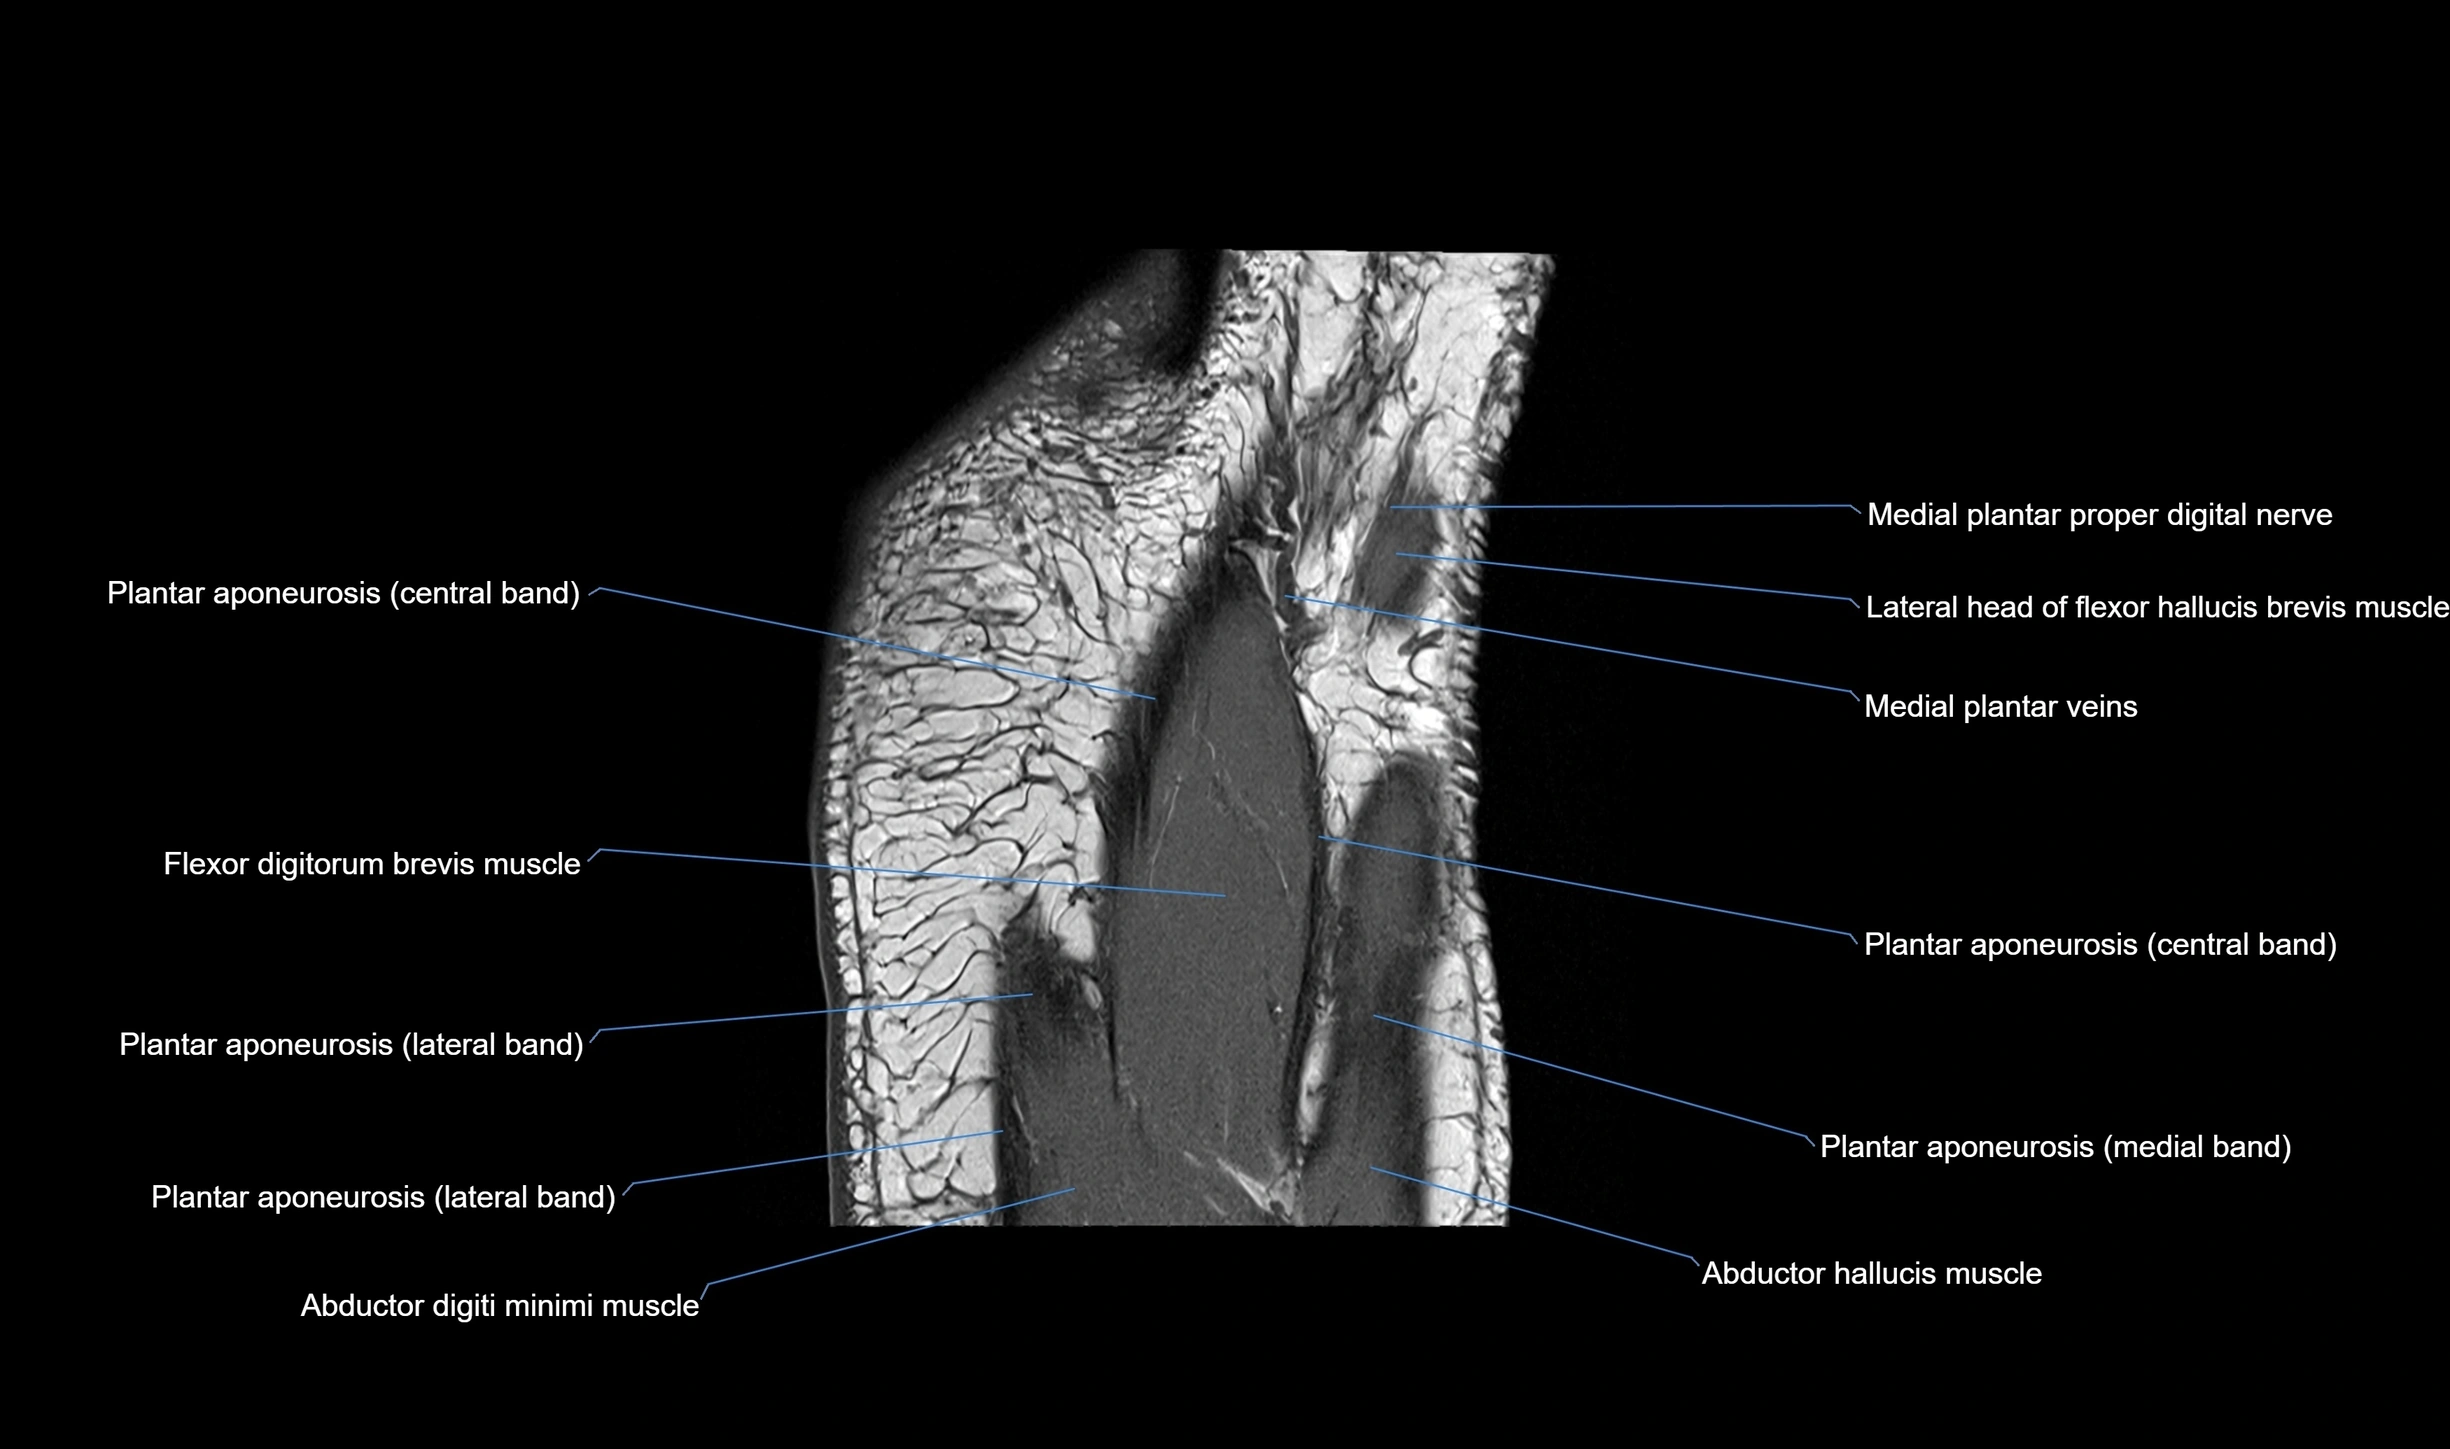

MRI image